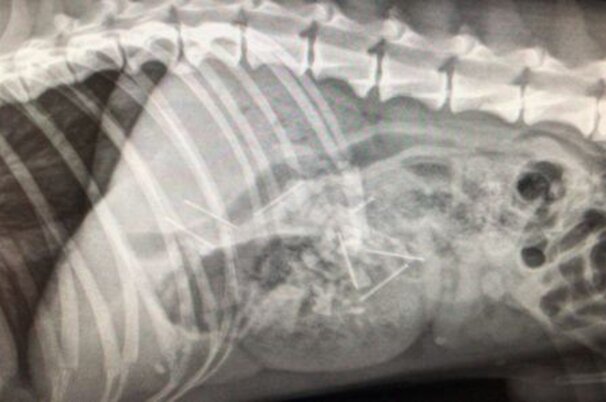

Ermittlungen wegen Tierquälerei